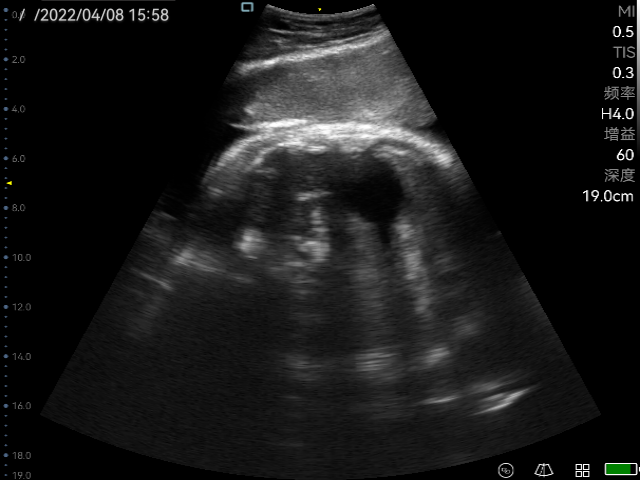

Obstetric ultrasonography is one of the routine prenatal examination items. The ultrasonic diagnostic instrument is used to scan various sections of the human body. According to the amplitude of the echo signal, real-time imaging is performed on the monitor, so it can detect the uterine appendages and the fetus. Through the biological measurement of the fetal head, abdomen, long bones, etc., the gestational age and the size of the fetus can be estimated. Through the observation of real-time dynamic ultrasound images, it is possible to detect whether the fetus has structural abnormalities, determine the degree of fetal malformation, evaluate the prognosis, whether clinical treatment is required to preserve fetal survival. For pregnant women with no abnormal performance within ten weeks, no ultrasound examination is required. For older and high-risk pregnancy, obstetric ultrasound examination must be performed regardless of the gestational age, which not only ensures the safety of the fetus, but also prepares for delivery. Ultrasound is widely used in obstetrics because of its non-radiation, simple operation, flexibility and convenience, high resolution, and moderate examination price.

The practical application of P50 in obstetrics

Perioperative period is helpful for doctors to assess the real-time labor processes of the placenta, amniotic fluid etc.

Ultrasonography in early, middle and third trimester, obstetric Doppler ultrasound, normal twin pregnancy, ultrasound diagnosis of common fetal structural malformations, twin pregnancy complications, abnormal pregnancy, abnormal pregnancy appendages, real-time monitoring of midwifery, etc.